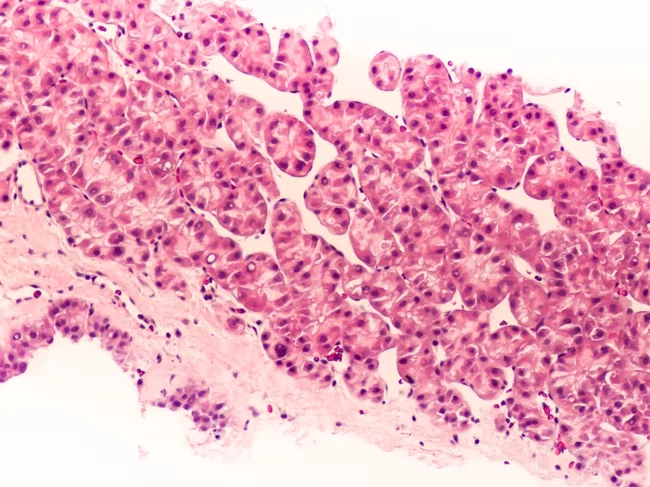

Photomicrograph of hepatocellular carcinoma

Rznomics receives US IND clearance for RZ-001 for hepatocellular carcinoma

Rznomics Inc. has received IND approval from the FDA for a phase I/IIa trial of RZ-001 for hepatocellular carcinoma (HCC). Read More